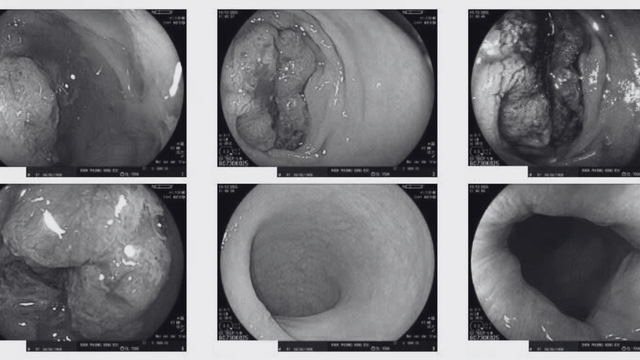

Đến tháng 12/2025, ông xuất hiện đau bụng tăng dần, đau khắp bụng, chướng bụng rõ, bí trung đại tiện, kèm theo hậu môn rỉ dịch hồng và buộc phải nhập viện cấp cứu. Qua nội soi trực tràng, các bác sĩ phát hiện khối u ung thư phát triển lớn, chiếm trọn lòng trực tràng, gây tắc ruột hoàn toàn. Bệnh nhân được chỉ định phẫu thuật cấp cứu làm hậu môn nhân tạo để giải phóng tình trạng tắc nghẽn, tránh nguy cơ vỡ ruột và nhiễm trùng ổ bụng đe dọa tính mạng.

Khối u ung thư phát triển lớn, chiếm trọn lòng trực tràng, gây tắc ruột hoàn toàn